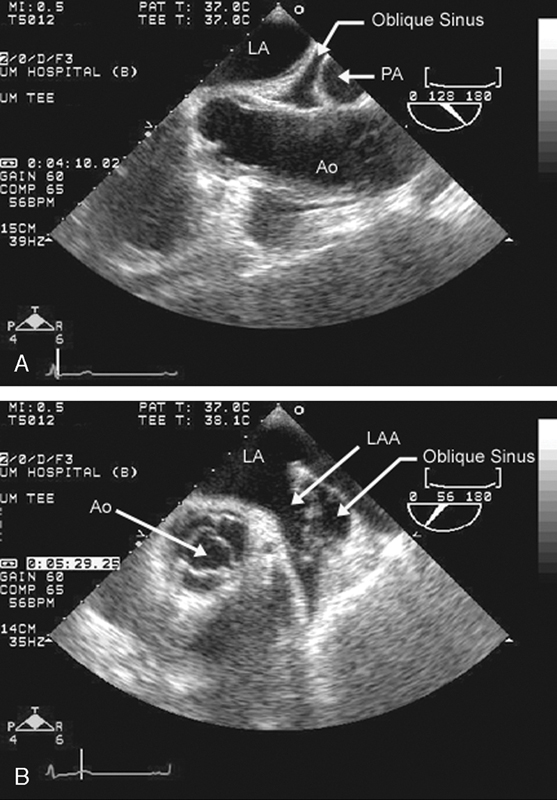

فحوصات تشخيصية لبعض امراض القلب والشرايين التاجية